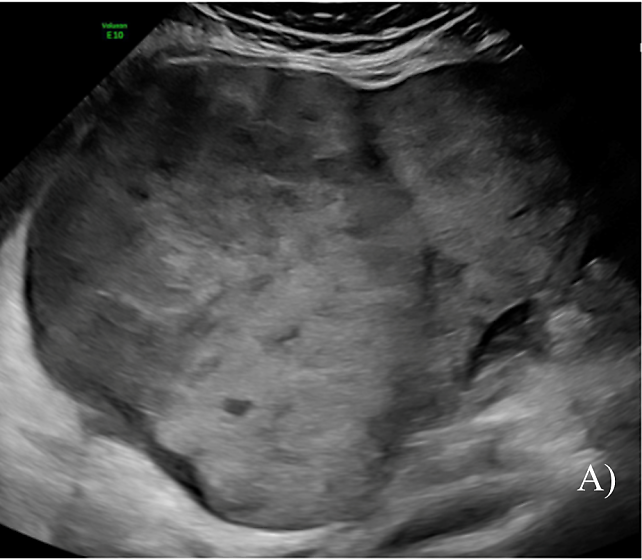

LGSOCs commonly appear as multilocular-solid (55%) or solid (32%) masses (Figure 4). Sonographic features typically include small calcifications in the solid tissue and papillations (32%).10

4

(A–E) Grayscale sonographic images of low-grade serous carcinoma (LGSOC). Arrow indicates echogenic foci consistent with calcifications. As reported by Moro et al., LGSOCs commonly appear as multilocular-solid (55%) or solid (32%) masses.10

In a retrospective analysis of preoperative ultrasound images of malignant serous ovarian tumors, Moro et al. reported an overlap in ultrasound appearance between BOTs and non-invasive LGSOCs, both presenting as cysts with papillary projections.10 Similarly, the authors reported an overlap in ultrasound characteristics between invasive LGSOCs and HGSOCs, as both tumor types appeared as multilocular-solid masses with non-papillary solid components or solid masses. However, HGSOCs were more likely to be solid than were invasive LGSOCs which, in turn, were more often multilocular-solid.10 Moreover, a considerable number of invasive LGSOCs presented hyperechoic foci, which were very rare in the other subclasses of malignant serous ovarian tumors.